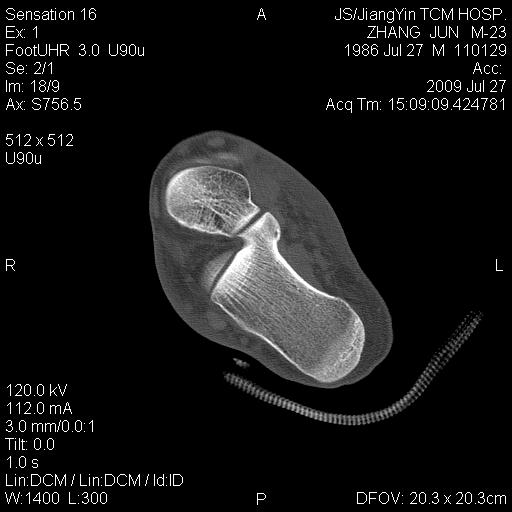

男性,23岁。外伤检查发现跟骨局限性密度减低,有无病理意义。请指教。

骨髓窦概念:是指松质骨内先天性骨小梁发育稀少,各组骨小梁间的骨小梁少或缺如,形成一空腔,内含有骨髓,称为骨髓窦,为正常解剖变异。骨髓窦以跟骨最多见,简称骨髓窦,其次见于股骨颈、股骨远端及髋臼上缘等处。

形成原因:跟骨窦的形成 跟骨示足弓的重要支点,承受着来自自身及负荷的重量。为了适应承受重量的力学需要,跟骨的结构十分精密合理。其骨小梁的发育有三组:①自跟距关节后缘向后下方呈斜向走行;②沿跟骨下方分布;③自跟结节处向前方伸展。三组骨小梁间有一个类三角形、圆形或椭圆形透亮区,即跟骨窦。

跟骨窦的表现:观察跟骨窦以侧位平片为佳。其特点是位于跟骨前部中央,跟骨沟后方,尖端向上,足弓后上部,承受重量轻的特定位置。窦的基底与跟骨下缘平行。与窦基底相当的跟骨下缘皮质密度高,呈致密带状或线状。窦内骨小梁稀少或缺如。边缘清楚整齐,无硬化。大小1-3cm。窦内有时可见营养沟。多数为单侧,少数双侧对称发生。窦周骨质正常。

鉴别诊断:1.跟骨囊肿 囊肿多位于跟骨后中部,与跟骨窦位置不同。呈圆形或椭圆形,囊内无骨小梁,高度透亮,膨胀生长,周边轻度硬化。2.单房性巨细胞瘤 破坏区边缘清楚,内无骨间隔。骨皮质变薄。临床上有疼痛。肿瘤多位于跟骨后部,肿瘤中心多在跟骨窦之后。3.跟骨结核 病变范围较小,病变呈不规则破坏,边缘模糊,无硬化。

跟骨原发骨化均出现在胚胎期23周,出生后已具有正常跟骨的雏形.7岁时,各骨性关节面,继发骨骺和骨性突起相继出现.男14岁、女12岁以后,跟骨的生长基本停止.暂时性发育性跟骨刺,跟骨多骨化中心,跟结节不规则和继发骨骺碎裂、硬化等发育时期的变异只出现在某个年龄段.而跟骨骨髓窦,跟距骨桥和致密骨岛则持续到成人.